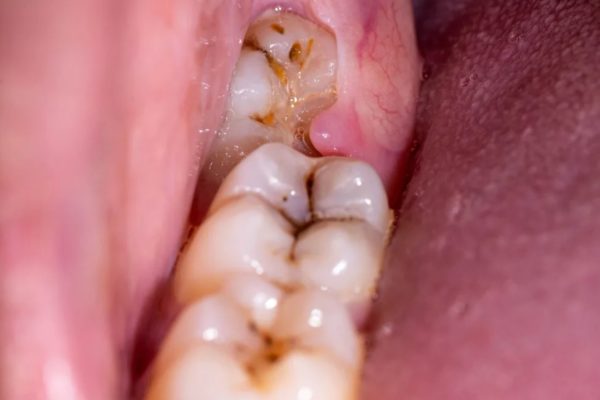

Khi mọc răng khôn có bị đau đầu, đau tai không? Quá trình mọc răng khôn có thể diễn ra êm đềm, nhưng ở nhiều người lại gây ra các triệu chứng đau nhức, sưng nướu, thậm ...

Mọc răng khôn có đau không? Dấu hiệu khi mọc răng khôn là gì? Mọc răng khôn (hay còn gọi là răng hàm số 8 hoặc wisdom teeth) là giai đoạn mà hầu hết ai trong chúng ta cũng phải trải ...